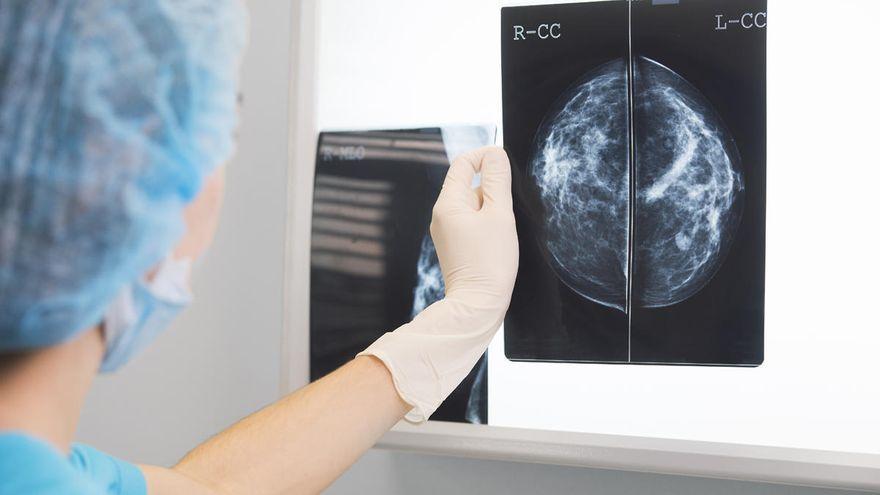

La Junta Directiva de La Asociación de Cáncer de Mama de Tenerife Ámate ha transmitido su «gran preocupación» ante los importantes retrasos que a su juicio se están produciendo en la atención hospitalaria y quirúrgica de esta enfermedad, para la que ha pedido «todos los recursos necesarios».

En un comunicado difundido este miércoles Ámate alude a que ha recibido muchas llamadas de personas afectadas de cáncer de mama que han expresado su preocupación ante los importantes retrasos que se están produciendo en la atención en consultas, quirófanos e incluso en anatomía patológica.

Muchas de estas personas comentan que, ante la falta de quirófanos, la espera para ser operadas puede llegar a ser de hasta tres meses, cuando se sabe que un diagnóstico precoz y su inmediato tratamiento aumenta la supervivencia de las personas afectadas por esta patología, añade.

Ámate es consciente de que la situación sanitaria actual, marcada por la pandemia de la covid-19, es extraordinaria y que se han de usar todos los recursos necesarios para intentar superarla pero, advierte, el cáncer también mata.

Por tanto, la asociación exige que se destinen todos los recursos que sean necesarios para el diagnóstico y posterior tratamiento del cáncer de mama y así solventar la actual situación.